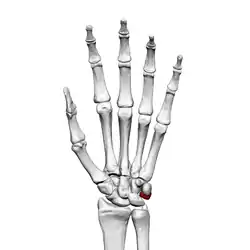

Left hand anterior view (palmar view). Triquetral bone shown in red.